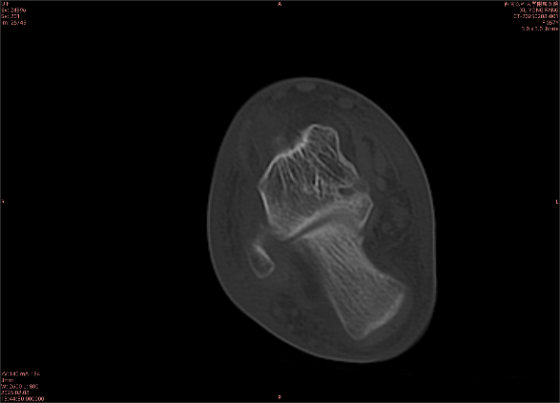

舉例圖像

圖1

專業(yè)解釋看不懂沒關(guān)系,大家看圖1和圖2就可以了,這是同一個(gè)患者跟骨的磁共振和CT圖像,圖1的紅色箭頭指示的黑線就是磁共振圖像顯示的骨折線,一目了然。而對比圖2的CT圖像上并未顯示異常。